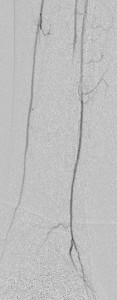

Key to images:

Bottom panel: Post intervention run-off arteriogram of the left lower extremity showing, from left to right, the proximal and distal segments of the re-opened left femoro-popliteal bypass (red arrows on images 1, 2, and 3). Contrast the full-column opacification of the below-knee left popliteal artery, arrowed blue on the 3rd image, and the enhanced visibility of the three-vessel subpopliteal domain to their vestigial appearances on the pre-intervention images, when they were poorly fed through collaterals.